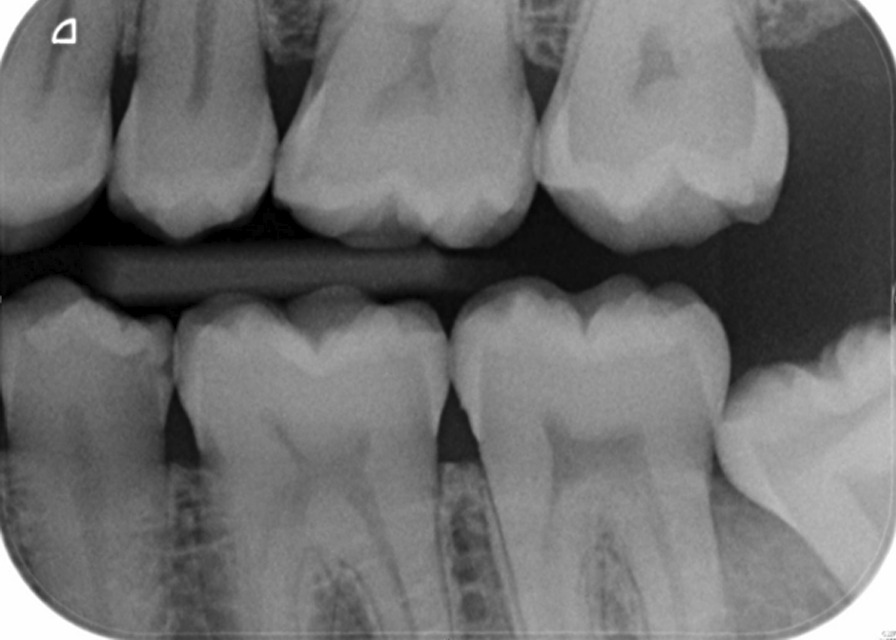

In this study, partial eruption or partial emergence of the mandibular third molar was determined by assessing the third molar position in relation to the adjacent second molar and the anatomical landmarks. The third molars were deemed to be partially erupted when one of the third molar cusps was positioned above the external oblique ridge or the occlusal plane level of the neighbouring second molar. In cases where these anatomical landmarks could not be assessed on the radiograph, the Cementoenamel Junction (CEJ) of the adjacent mandibular second molar in relation to the marginal ridge position of the adjacent third molar was also used to obtain information on the eruption status of mandibular third molars and its depth of impaction. This assessment method is a modified description of the Pell & Gregory classification and class I B, class II B, class III A and B from the original Pell & Gregory categorisation were included [3]. This was applied to all third molar angulation types (mesial, distal, vertical, horizontal and transverse). Figure 1 illustrates an impacted and partially erupted mandibular third molar on a bitewing radiograph contacting the second mandibular molar below the CEJ. Figure 2 shows a section of a panoramic radiograph of a mandibular third molar that was deemed partially erupted. The external oblique ridge or bony anterior border of the ramus that appears radiopaque and is located on the outer aspect of the mandible which runs from the ramus to the first molar is indicated with a white dashed line.

Fig. 1.

Left bitewing radiograph of impacted and partially erupted mandibular third molar contacting the adjacent second molar below the CEJ